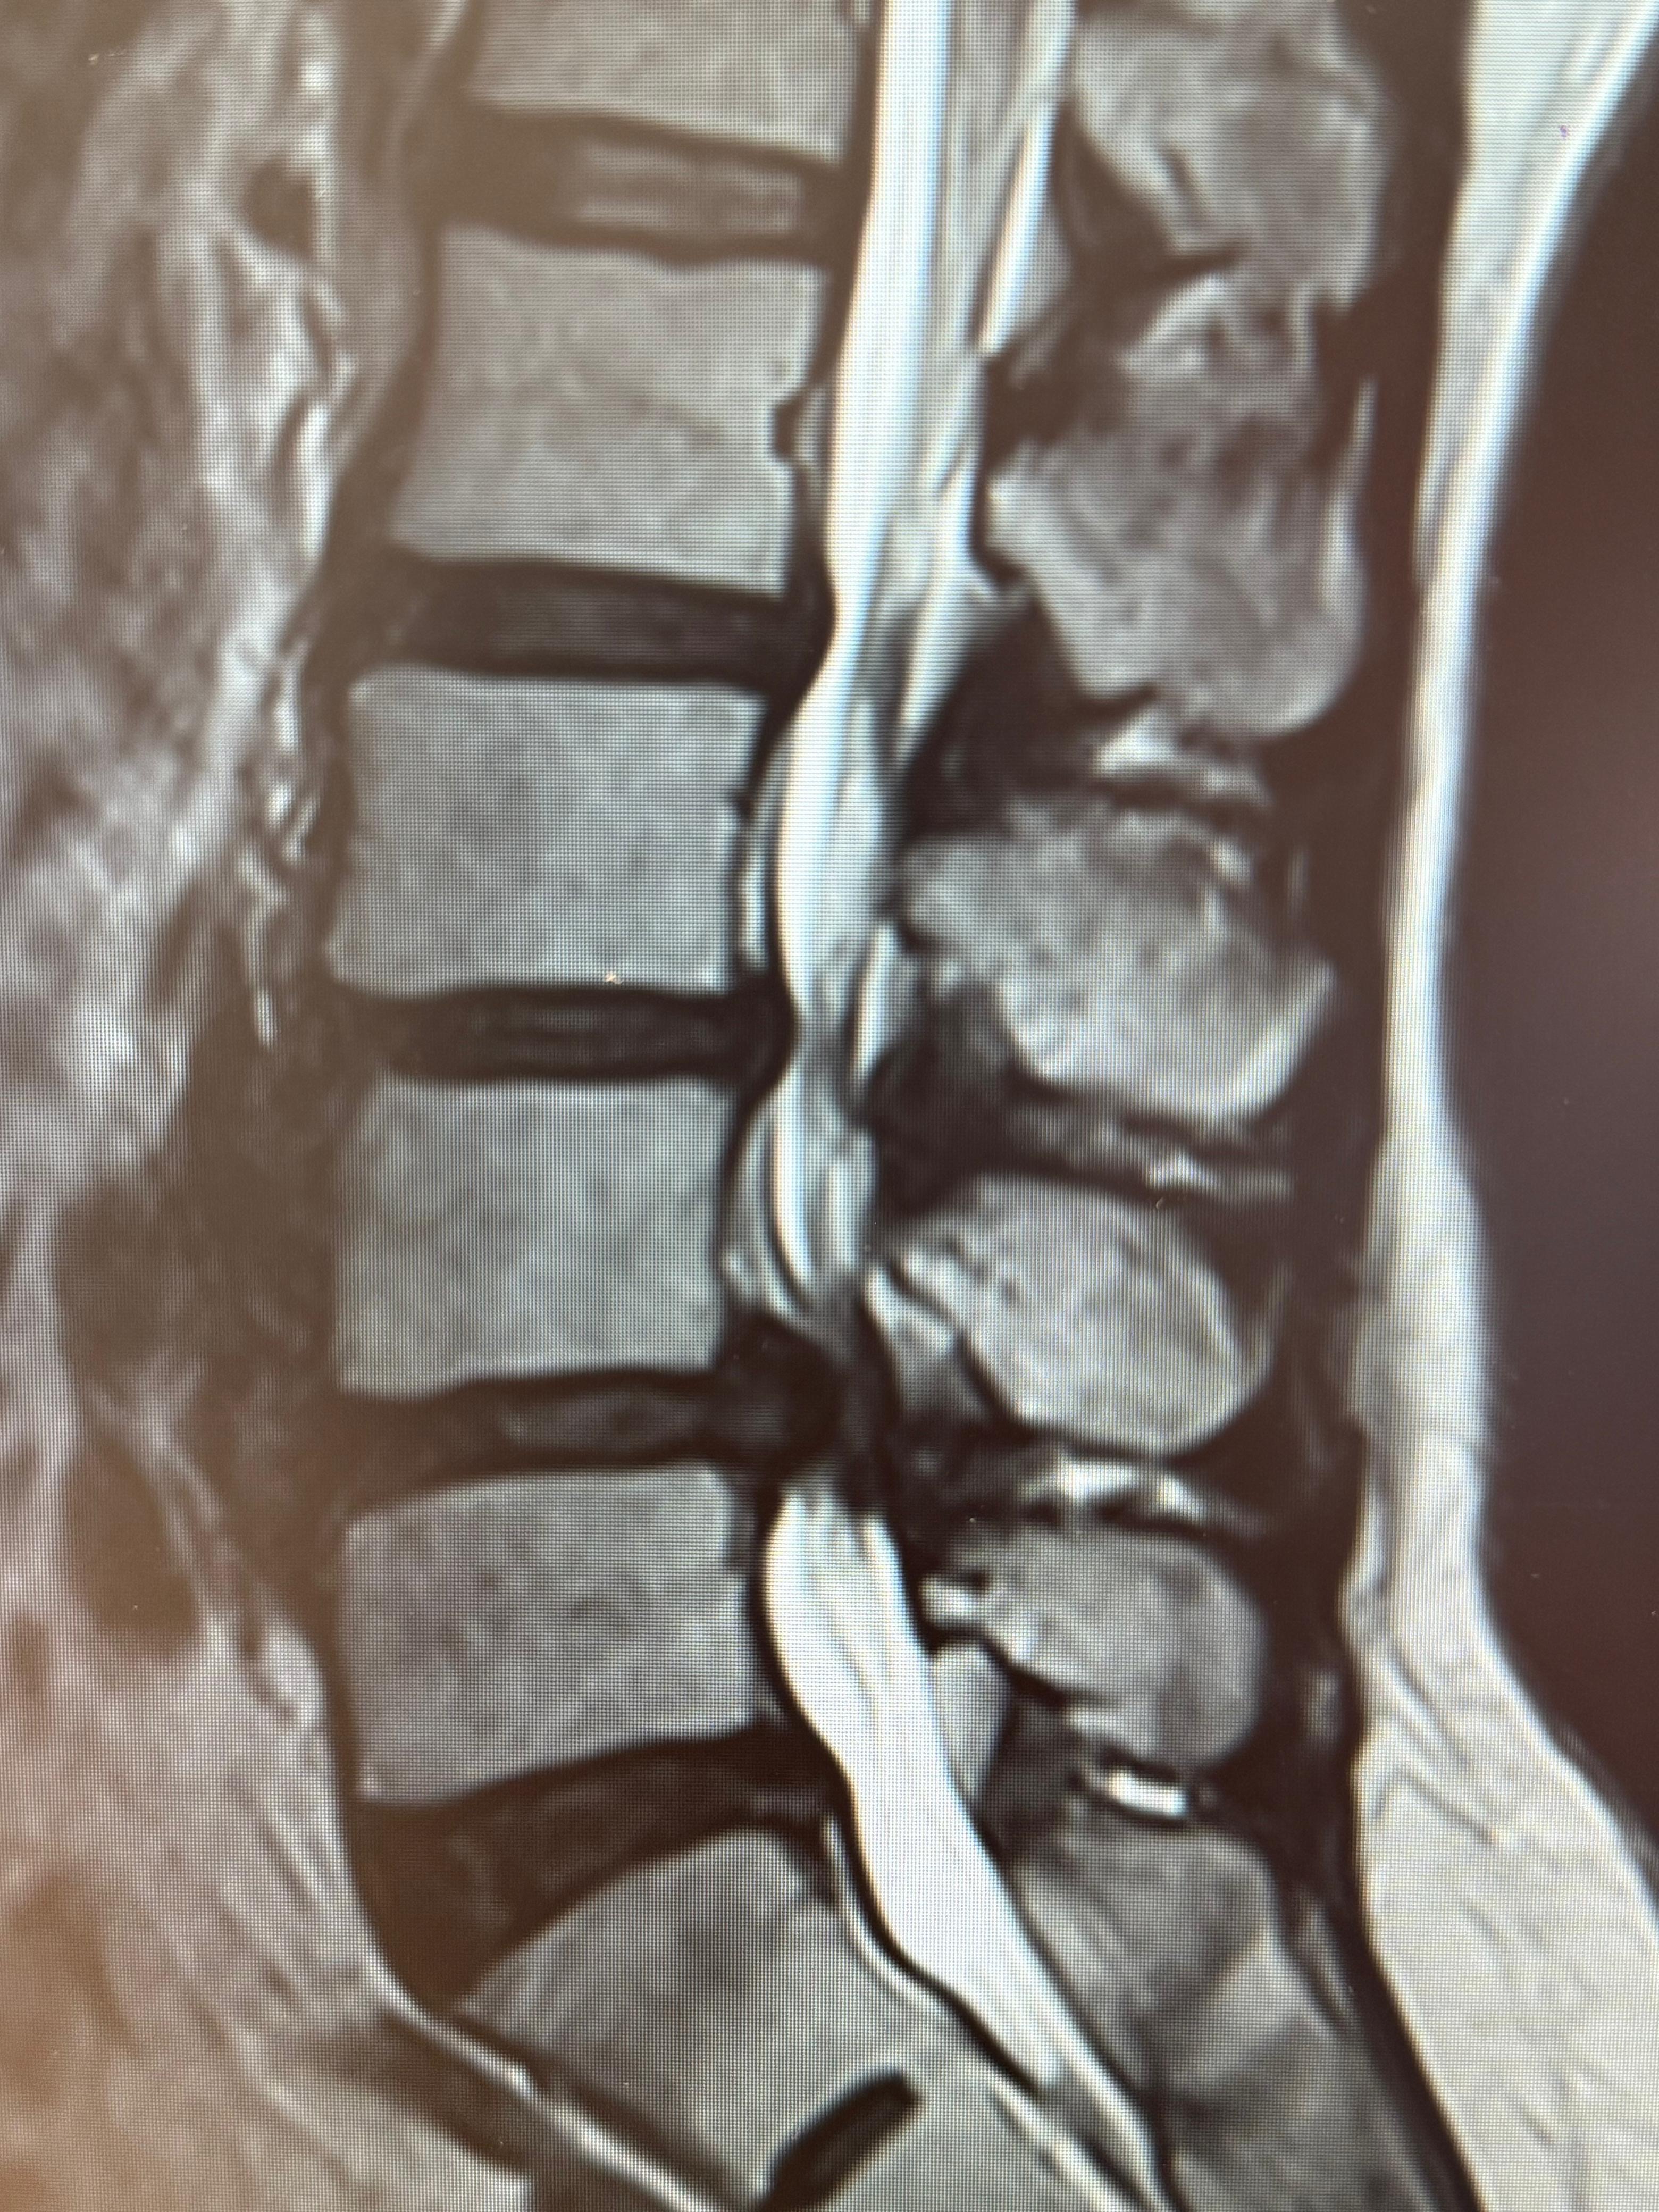

Mi mamá lleva más de 4 años viviendo con un dolor constante en la espalda baja debido a hernias . Este dolor le ha impedido caminar con normalidad; cuando lo intenta, siente un entumecimiento en la entrepierna y debe detenerse, dice que siente como hormigueo. Cada paso se ha convertido como en un reto y esto afecta su vida diaria. Ya la habían tratado para este dolor y solo la mandaban a terapia, le recomendaron hacer ejercicio antes de saber que era hernia y lo hacía aunque le doliera para que mejorara, y fue hasta este año que se logró hacer una resonancia magnética con el sector público y pudimos ver que era la hernia discal, que desafortunadamente está muy avanzado, al punto que hoy en día apenas y puede dar unos pasos y después se le entume sus piernas y pierde fuerza en ellas y ya no puede continuar caminando

Ella siempre ha sido una mujer activa, vendía comida los fines de semana, una barbaboca muy rica por cierto! pero hoy ya no puede realizar muchas de las actividades que antes hacía. Además, este año fue diagnosticada con diabetes, (hace 3 meses) lo cual vuelve su situación aún más delicada , el médico en el sector público que la atiende, le dijo también que si se opera tiene un 75% de posibilidad de salir bien y no tiene empatía para explicar las cosas, que puede no volver a caminar o incluso morir mientras le ponen la anestesia general, mi mamá llegó asustada con mi papá, y aunque no tenemos los recursos para ingresarla a otro hospital, por ahora estamos en espera de esa solicitud del sector público :/ por qué mi mamá ya no aguanta el dolor y aunque tiene miedo también tiene fe en Dios en que todo saldrá bien

Actualmente está en seguimiento (sector público), el dolor ha ido avanzando cada día más, se entumece la entrepierna, y no puede caminar con fluidez

Por eso estoy recurriendo a esta campaña, les pido de todo corazón que si está en su voluntad de ayudar no importa el monto o aunque sea compartir esta publicación se los agradecería, me encantaría poder ayudarle a recuperar su movilidad a mi mamá y más poder llevarla a un sitio donde puedan tratarla con más empatía y humanidad, y lograr ya hacerle la cirugía que requiere para que vuelva a caminar, nosotros ya tenemos los análisis médicos, y el diagnóstico que hicimos por parte del seguro este año, yo sé que no siempre se puede con la parte económica y aquí existen muchos casos y quizá el mío no sea el más grave, pero es mi mamá, y para mí lo es… :( hoy recurro a ustedes para que con su apoyo y generosidad pueda operarse lo antes posible, les estaré actualizando su estatus y avance médico